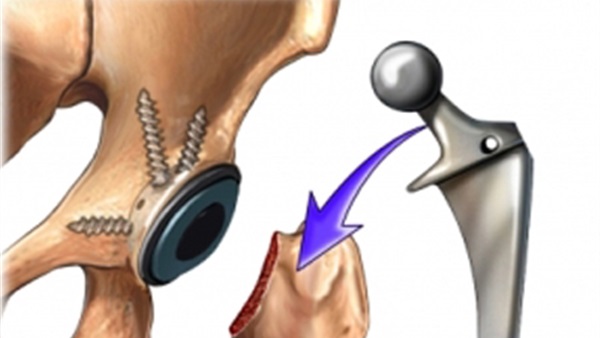

هذا النوع من الأعضاء البديلة هو أكثر طرف بديل للركبة شيوعاً ويستبدل مفصل الركبة بشكل كامل: يتم استبدال سطوح المفصل الخاصة بعظم الفخذ وعظم الظنبوب وأحيانا الرضفة المهم في هذا السياق أن تكون أربطة الركبة المثبتة للمحور كالرباط الخارجي والداخلي محافظ عليها و فعالة بهذا يمكن للمرء أن يزرع هذا العضو البديل حتى لو كان الرباط الصليبي الأمامي مدمر الأربطة الخارجية والداخلية تساهم بشكل حاسم في توازن الركبة حينما يكونان الرباط الصليبي الأمامي والخلفي غير ثابتين يمكن زراعة عضو بديل خلفي مثبِّت هذا العضو يتبنى وظائف الرباط الصليبي من خلال تحويل ضغط الفخذ للخلف والظنبوب للأمام عمليات الركبة الصناعية.

الهدف من عملية استبدال مفصل الركبة هو علاج تآكل الغضروف في مفصل الركبة، الذي يحدث غالباً نتيجة لالتهاب المفاصل المزمن على إختلاف أنواعه، و يتم اٍجراء عملية استبدال مفصل الركبة تحت تأثير التخدير العام أو الموضعي، ولكم كم سعر مفصل الركبة الصناعي هذا ما سنتعرف عليه بالتفصيل هنا:

تكلفة تركيب طرف اصطناعي جزئي للركب(استبدال جزئي للركبة / استبدال):14.000 €

تكلفة عمليات تغيير مفصل الركبة:15.500 €

تكلفة جراحة مراجعة الاستبدال الكامل للركبة:17.800 €